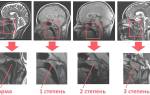

Сразу стоит оговориться, что необходимость операции никак не связана со степенью аденоидов. У некоторых детей при 2 степени болезни наблюдается сильно затрудненное дыхание и частые ЛОР-болезни, другие же и при 3 степени чувствуют себя удовлетворительно и хорошо поддаются консервативным методам лечения. Так стоит ли применять удаление и когда это надо делать в обязательном порядке?